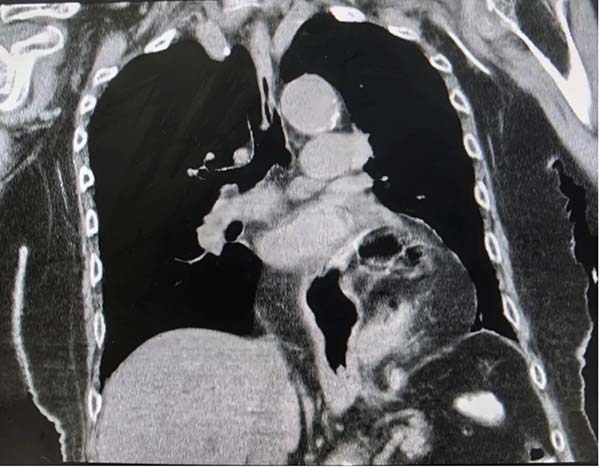

近日,北京朝阳医院普外中心疝和腹壁外科成功为一名92岁高龄的危重食管裂孔疝患者李老先生(化名)实施手术。该患者因大部分胃部“跑”进胸腔形成扭转,长期无法进食,生命垂危。在医院多学科团队的保驾护航下,普外中心疝和腹壁外科副主任杨慧琪团队勇闯手术禁区,将患者的胃成功复位,目前老人正在康复中。

李老先生因罹患食管裂孔疝,其大部分胃部通过膈肌缺损处突入胸腔,并发生胃扭转,这不仅导致老人无法进食,身体日渐消瘦,更随时有缺血性坏死的风险,病程复杂且凶险。家属带着老人辗转多家医院,均因超高龄、手术风险过高而被告知难以收治。

患者相关影像